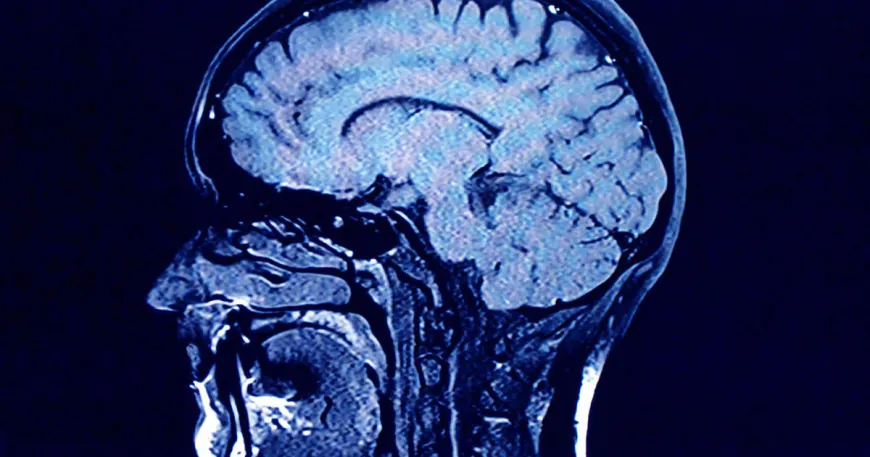

Study finds growing levels of microplastics in human brains